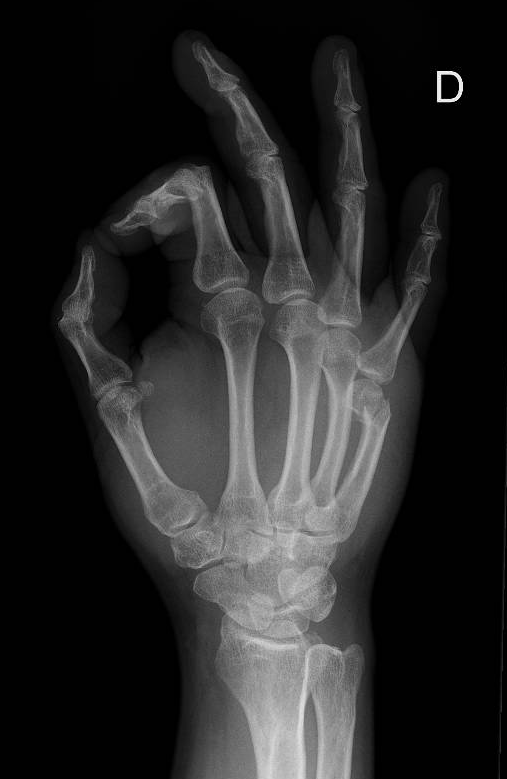

Fracture du Boxer

Image 2 : réalisée par M. Karakus

Images proposée par Matthieu Karakus (HIB)